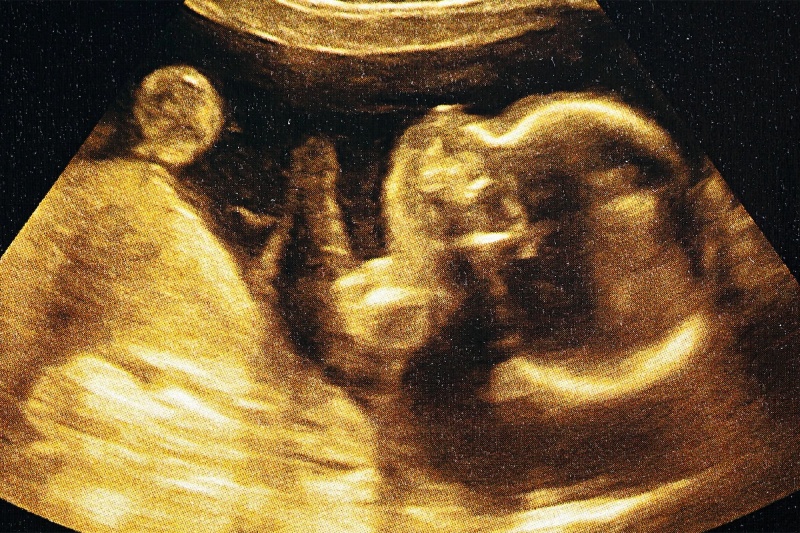

یک کودک که وقتی هنوز در رحم مادر بود، تحت درمان برای نوعی اختلال ژنتیکی نادر با احتمال مرگ بالا قرار گرفت، اکنون بیش از دو سال عمر کرده و هیچ علامتی از بیماری در او دیده نمیشود.

براساس مطالعهی جدیدی که در مجلهی پزشکی نیوانگلند منتشر شده، این اولین بار است که بیماری آتروفی عضلانی نخاعی (SMA) پیش از تولد تحت درمان قرار گرفته است. کودک مورد بحث بهطور خاص مبتلا به SMA نوع ۱ بود که شایعترین و شدیدترین نوع این بیماری است. پیشآگهی این بیماری بسیار ضعیف است و معمولاً پیش از دومین سالگرد تولد کودک به مرگ منجر میشود.

پس از انجام آزمایشات ژنتیکی در دوران بارداری، مشخص شد که نوزاد مورد مطالعه در معرض خطر ابتلا به SMA نوع ۱ قرار دارد. والدین این کودک قبلاً یک فرزند مبتلا به SMA نوع ۱ داشتند که فوت کرده بود. آزمایشها نشان داد که جنین در حال رشد نیز دارای جهش در ژنهای SMN1 در هر دو کروموزوم است.

تا پیش از این، داروی ریسدیپلام فقط پس از تولد به بیماران داده میشد، اما در مورد خاص اخیر، به درخواست والدین، در دوران بارداری به جنین داده شد. از آنجایی که ریسدیپلام فقط برای کودکان بالای دو ماه تأیید شده است، سازمان غذا و داروی آمریکا اجازه استفاده ویژه از این دارو را در دوران جنینی صادر کرد.

مادر کودک در هفتهی ۳۲ بارداری، شروع به مصرف روزانهی ریسدیپلام به مدت شش هفته کرد. آزمایش در زمان تولد نشان داد که این دارو واقعاً در دوران بارداری وارد سیستم کودک شده است. تقریباً یک هفته پس از تولد، نوزاد مصرف خوراکی دارو را آغاز کرد.